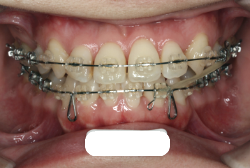

「前歯が重ならない」という主訴で来院したケースです。診断の結果、「重症の開咬」と判明しました。

この方の場合は、マルチブラケット装置は、歯の位置づけを3次元的に正確に行うことの出来る最善の矯正方法です。したがって開咬の治療も、形の改善としては問題なく行うことが出来ます。しかし、開咬が他の症状と少し違う点は、舌や唇の動かし方に問題があることから生じた症状なので、この問題を放置したまま形だけを作っても、時間が経つと簡単に後戻りしてしまうという問題です。つまり、マルチブラケット法で形態の矯正をするのと同時に、原因となっている筋肉の動きを正常に修正しなければなりません。この筋肉の動きを正常に修正する治療が、"筋機能訓練療法(Myo-functional therapy:略してMFT)"といわれるものです。

筋機能訓練療法は、筋機能訓練療法士という特別なトレーニングを積んだ歯科衛生士が行います。内容的には、いろいろなメニューがあり、簡単なものから始めて少しずつ筋肉の力を強めていき最終的には、無意識に起きる舌の突出をなくし、正しい摂食嚥下運動を獲得するまでトレーニングしていきます。この症例は、もちろん筋機能訓練にもしっかり取り組みました。治療後は開咬が改善しただけでなく、出っ歯の症状もなくなり唇の審美性が大幅に改善しました。もちろん奥歯の噛み合わせも正しい状態が確立しています。